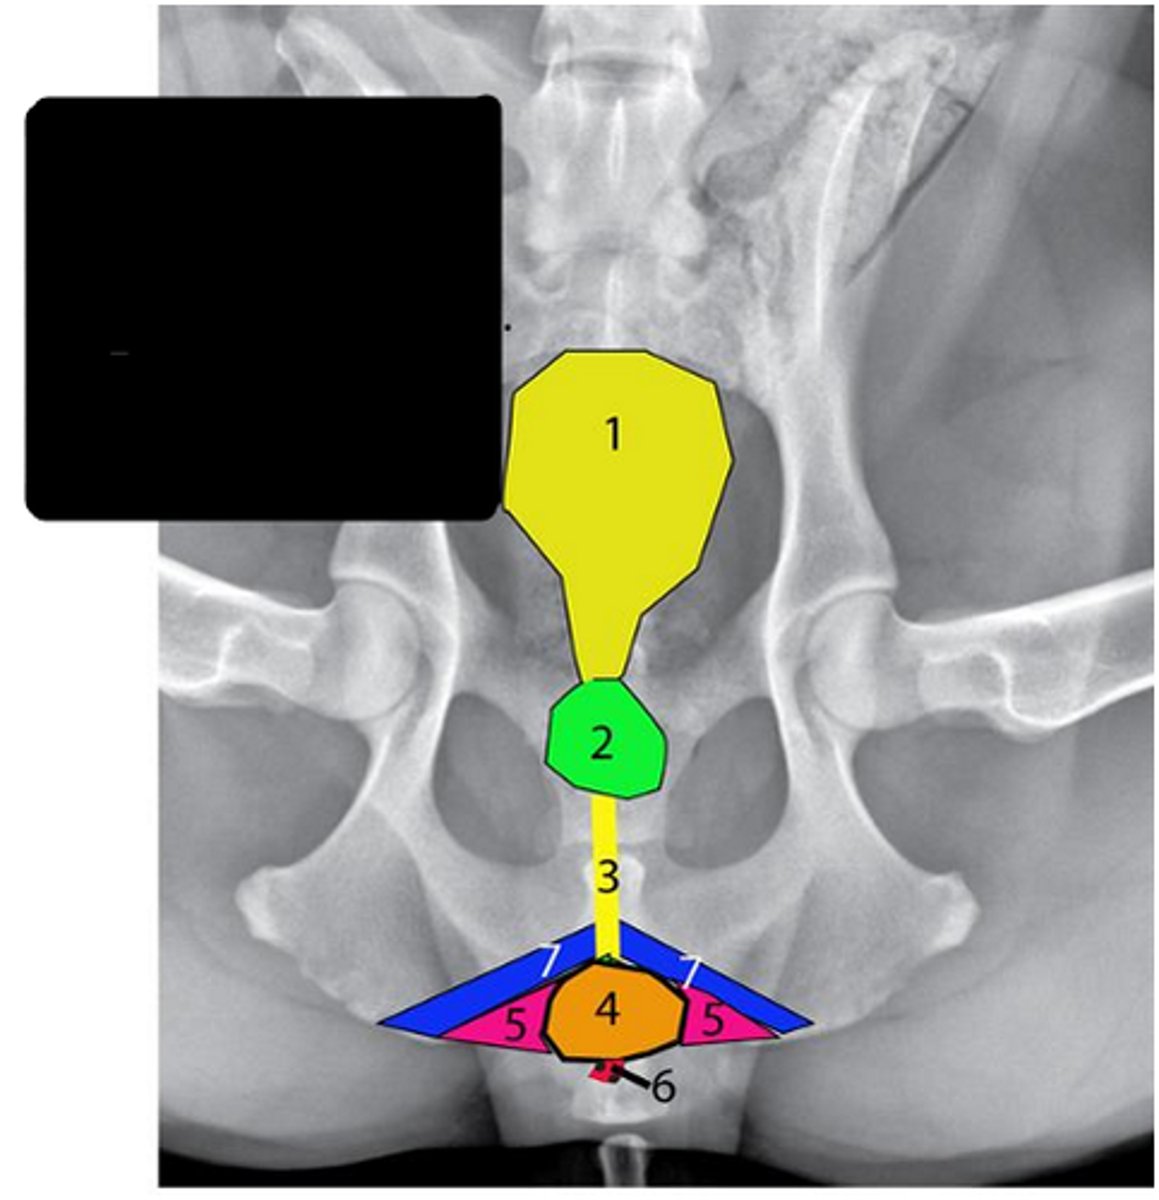

Bladder

Identify #1

Prostate

Identify #2

Urethra

Identify #3

Bulbospongiosus muscle

Identify #4

Ischiocavernosus muscle

Identify #5

Retractor penis muscle

Identify #6